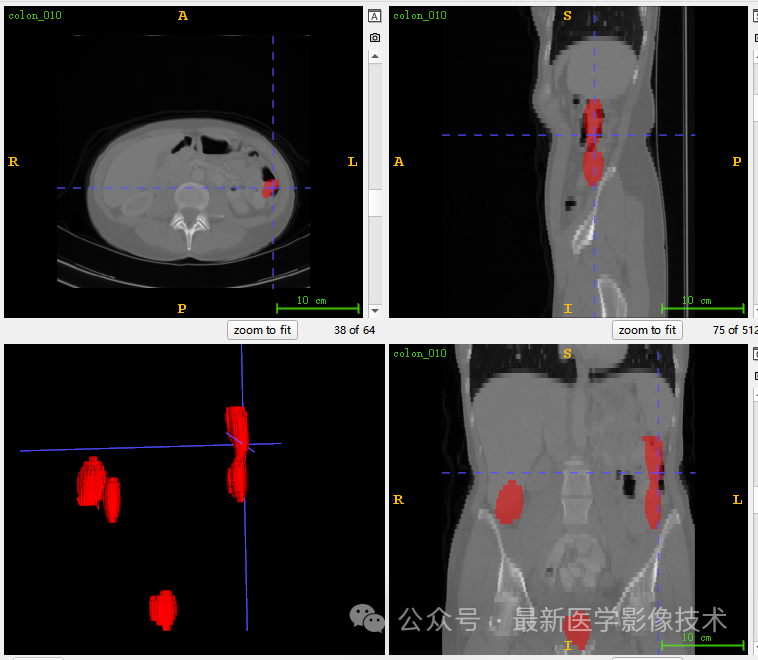

6、测试集分割结果